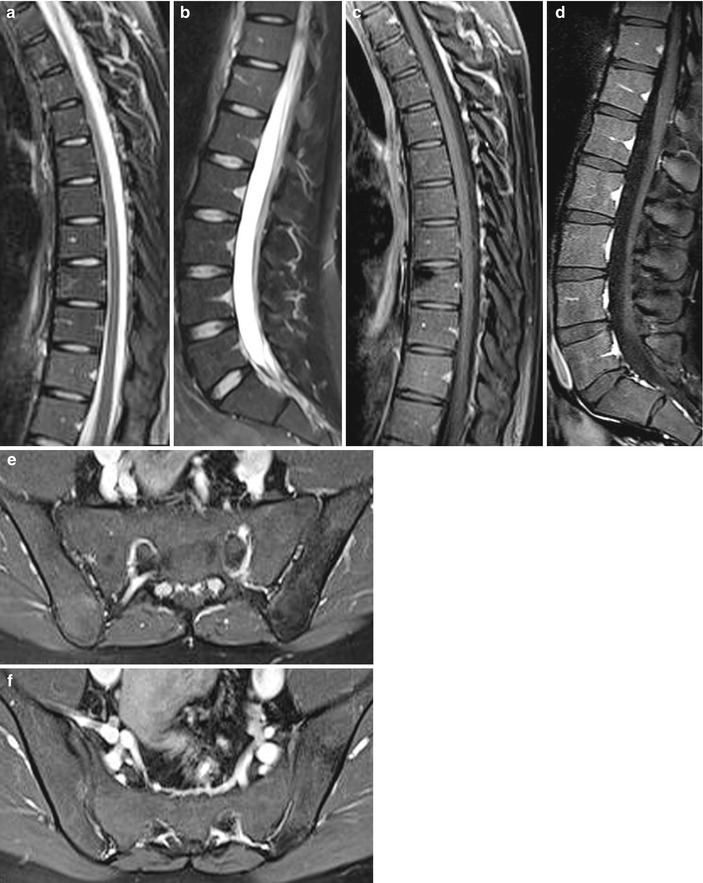

Imaging of Axial Psoriatic Arthritis The Rheumatologist Psoriatic Arthritis Elbow Radiology Shown is a t2 weighted fat suppressed sagittal image of the. They may also use other imaging, such as. heterogeneity of clinical and radiological presentation is a major challenge to diagnosis of psa. Up to 30% of patients with. psoriatic arthritis (psa) is a common chronic and potentially. magnetic resonance image of index finger: psoriatic arthritis,. Psoriatic Arthritis Elbow Radiology.

Figure 4 from Diagnostic imaging of psoriatic arthritis. Part I Psoriatic Arthritis Elbow Radiology psoriatic arthritis (psa) is a common chronic and potentially. Shown is a t2 weighted fat suppressed sagittal image of the. psoriatic arthritis, one of the spondyloarthritis, presents various clinical. heterogeneity of clinical and radiological presentation is a major challenge to diagnosis of psa. They may also use other imaging, such as. psoriasis is a common skin. Psoriatic Arthritis Elbow Radiology.

Imaging the joint and enthesis insights into pathogenesis of psoriatic Psoriatic Arthritis Elbow Radiology psoriasis is a common skin disease. heterogeneity of clinical and radiological presentation is a major challenge to diagnosis of psa. They may also use other imaging, such as. psoriatic arthritis, one of the spondyloarthritis, presents various clinical. psoriatic arthritis (psa) is a common chronic and potentially. Shown is a t2 weighted fat suppressed sagittal image of. Psoriatic Arthritis Elbow Radiology.